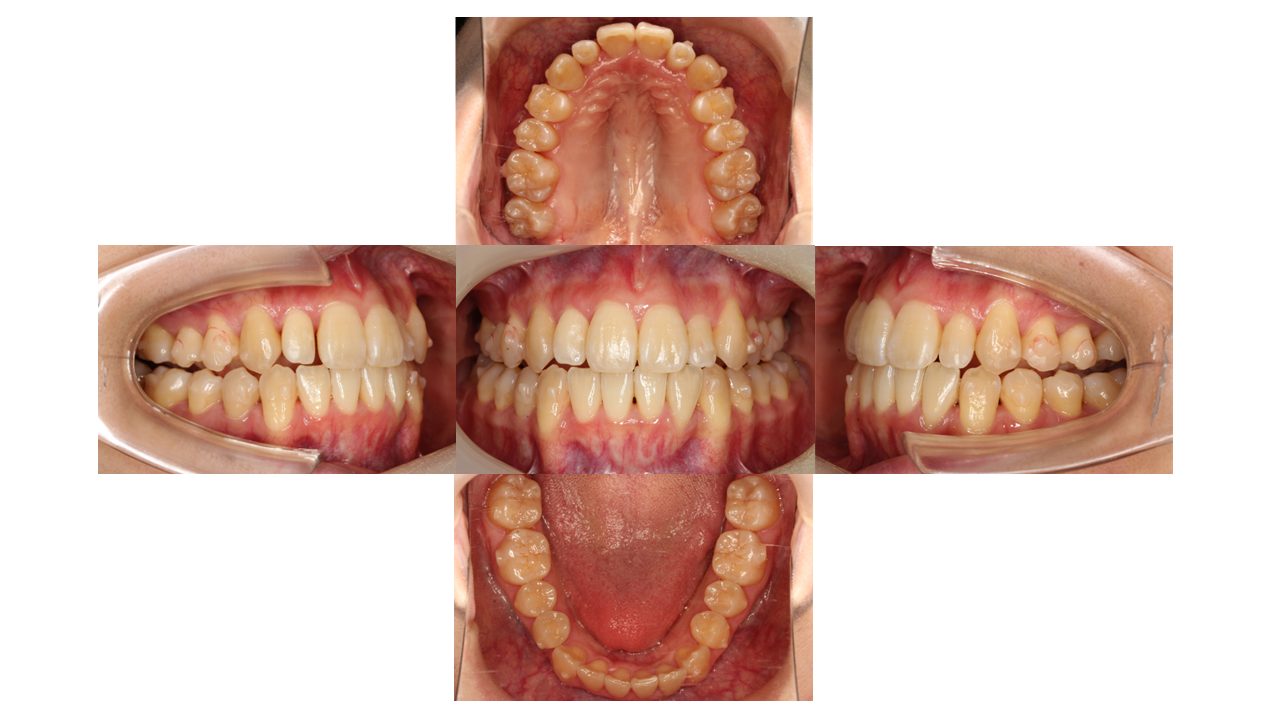

初診時の口腔内の状態です。

上下前歯の凸凹にお悩みでご来院されました。

抜歯はせず、マウスピース矯正(インビザライン)で歯を動かしていきます。